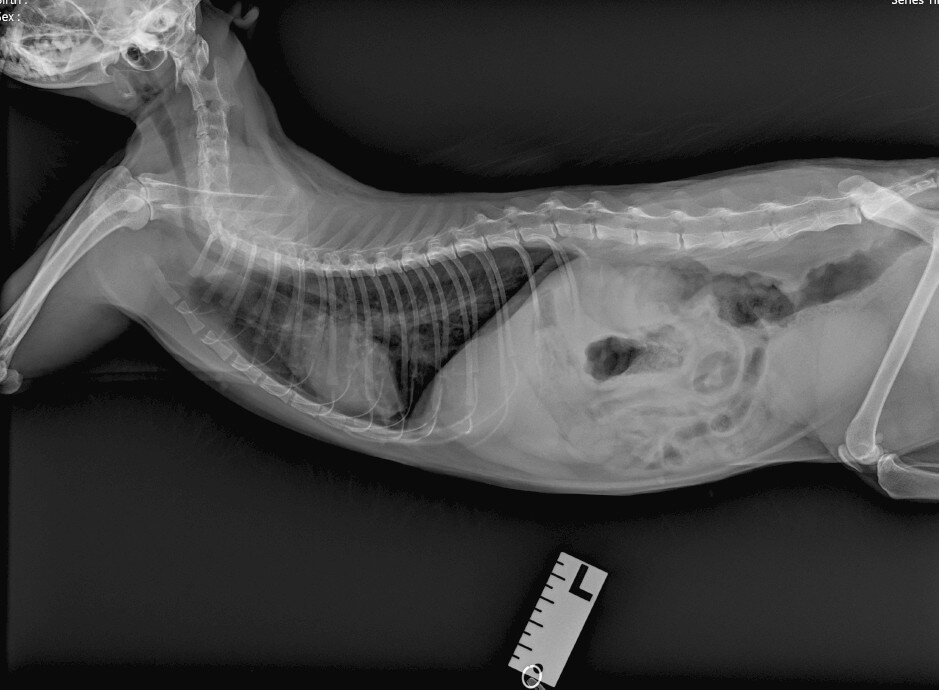

На сегодняшний день долг в клинике 800 за рентген кошки Салли с сердечной отдышкой. Врач назначил УЗИ СЕРДЦА, никак не может женщина сейчас себе его позволить. Кошечка Салли: очередной пример, когда ветеринары не дают пояснений волонтеру...

Салли